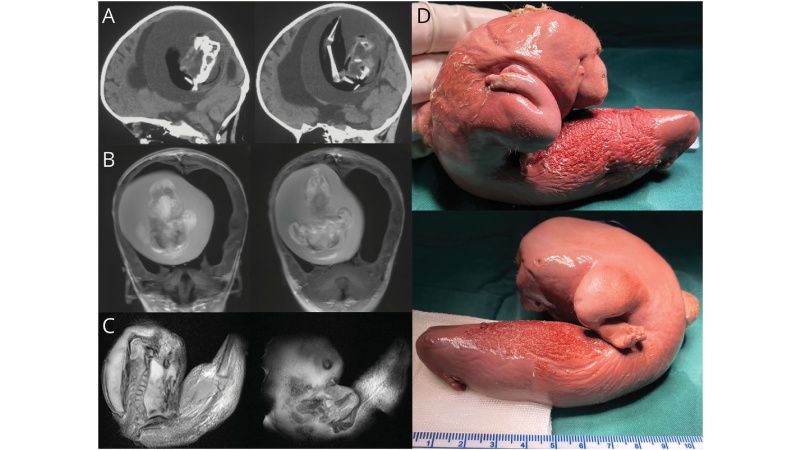

▲女嬰頭骨內有10.16公分的胎兒,而且胎兒已經長出脊椎、上肢、指甲和腿骨。(圖片擷取自《神經學》)

女嬰已經1歲,但卻有動作發展遲緩以及腦積水的狀況,腦積水會導致頭圍增大、嗜睡和癲癇。女嬰被送往醫院進行電腦斷層掃描後,發現頭骨內有10.16公分的胎兒,而且胎兒已經長出脊椎、上肢、指甲和兩根腿骨(股骨和脛骨),醫師推測胎兒已經在女嬰體內發育了好幾個月。

病例報告中寫道嬰兒頭部的腫塊是「畸形的單絨毛膜雙羊膜雙胞胎」,是由未分離的胚泡產生的,意即原本應該要分別獨立成長的胎兒的細胞團黏在一起,「連體部分發育成宿主胎兒的前腦,並在神經板折疊過程中包覆另一個胚胎。」神經板是一種在早期發育中形成並產生神經系統的結構。

經過手術後,院方已經將女嬰頭中的胎兒肢體取出。但病歷報告並無描述患童手術後的詳細狀況。目前尚不知對女嬰的健康狀況是否會造成其他影響。